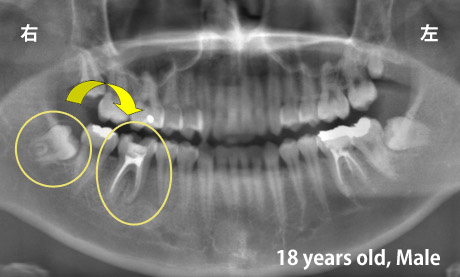

適切な条件がそろえば、歯の移植が可能です。歯の移植とは、治療することができない歯を抜いて、その場所へ本人の親知らずなどの歯を移す治療です。例えば、下のパノラマエックス線写真は18歳の男子です。右下の第一大臼歯が割れて痛みを伴って来院されました。この歯の保存できないと判断して、その歯を抜歯し,後ろにあるまだ生えていない親知らずをそこへ移植しました。移植の適切な条件とは、患者さん年齢が概ね40歳以下であること、口腔内に適切なドナー歯(主に親知らず)があること、移植歯(ドナー歯)と移植部位(受容側)の大きさが適合すること、などです。

| 年齢・性別 | 18歳 男性 |

| 主訴 | 第一大臼歯が割れてしまっていて治療することが困難 |

治療前のレントゲンの様子